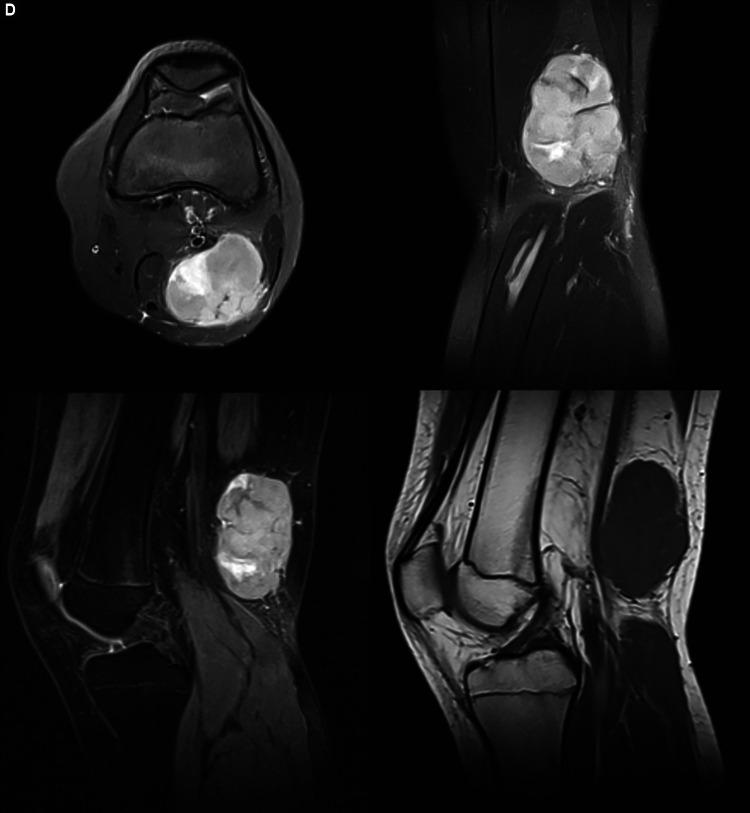

There is a relatively high incidence of patients recalling an injury before the appearance of a musculoskeletal (MSK) mass, especially in the hand and upper limb. Despite numerous reports of such cases, no clear pathogenetic mechanism has been elucidated to explain this. A tumour may be pre-existing, with the injury bringing the patient's attention to it, or develop coincidently following trauma. Alternatively, injury or the resultant reparative mechanisms may initiate or accelerate tumour formation. Following such a case presenting to our unit, a narrative review of the literature was conducted to determine what evidence existed to support or refute these hypotheses. This is presented along with the case. Though trauma as a cause of MSK tumours cannot be excluded, there is a lack of scientific evidence to support this theory, and further research in the field of pathophysiology and molecular biology is necessary. It is important that clinicians caring for trauma patients maintain a high index of suspicion for alternate diagnoses. A local injury may mask tumour development and lead to the incorrect conclusion that persistent symptoms are the result of failure to recover from the injury, rather than having a more sinister explanation.

有相当一部分患者在肌肉骨骼(MSK)肿块出现之前回忆起曾受过伤,尤其是在手和上肢部位。尽管有许多此类病例的报告,但尚未阐明明确的致病机制来解释这一现象。肿瘤可能原本就存在,受伤使患者注意到它,或者在创伤后 coincidently 发生。或者,损伤或由此产生的修复机制可能引发或加速肿瘤形成。在我们科室遇到这样一个病例后,对文献进行了叙述性综述,以确定有哪些证据支持或反驳这些假设。现将其与病例一同呈现。虽然不能排除创伤是MSK肿瘤的病因,但缺乏科学证据支持这一理论,因此在病理生理学和分子生物学领域有必要进行进一步研究。重要的是,治疗创伤患者的临床医生要对其他诊断保持高度怀疑。局部损伤可能掩盖肿瘤的发展,并导致错误的结论,即持续症状是受伤后未能恢复的结果,而不是有更险恶的原因。